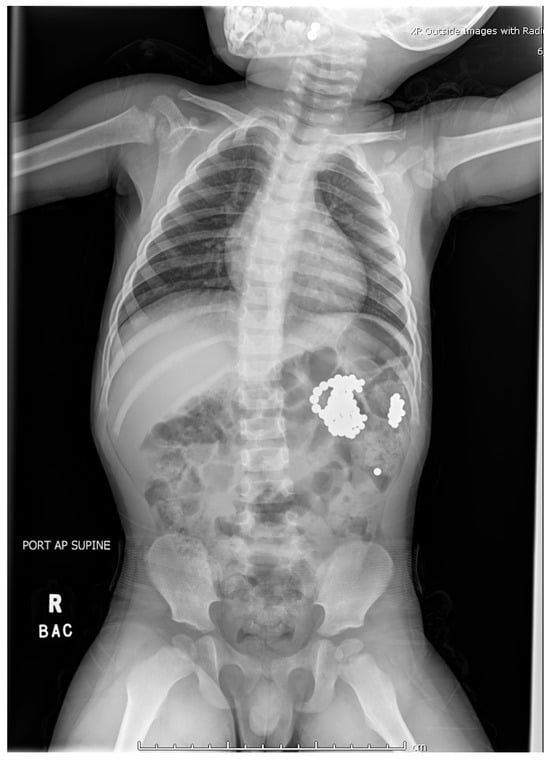

Plain radiographs demonstrated metallic densities clustered in the oropharynx, stomach, and small bowel (Figure 1). Recognizing the risks of gastrointestinal perforation and necrosis, the ED team initiated immediate multidisciplinary consultations with otolaryngology, gastroenterology, and general surgery. Magnet ingestions have been increasingly reported in pediatric literature due to their accessibility and the unique risks they pose to gastrointestinal tissues [4,5,6,7,8,9,10].

Figure 1. The radiograph from outside hospital reveals two magnets trapped in the oropharynx, with additional magnets overlying the distal stomach and proximal small bowel.